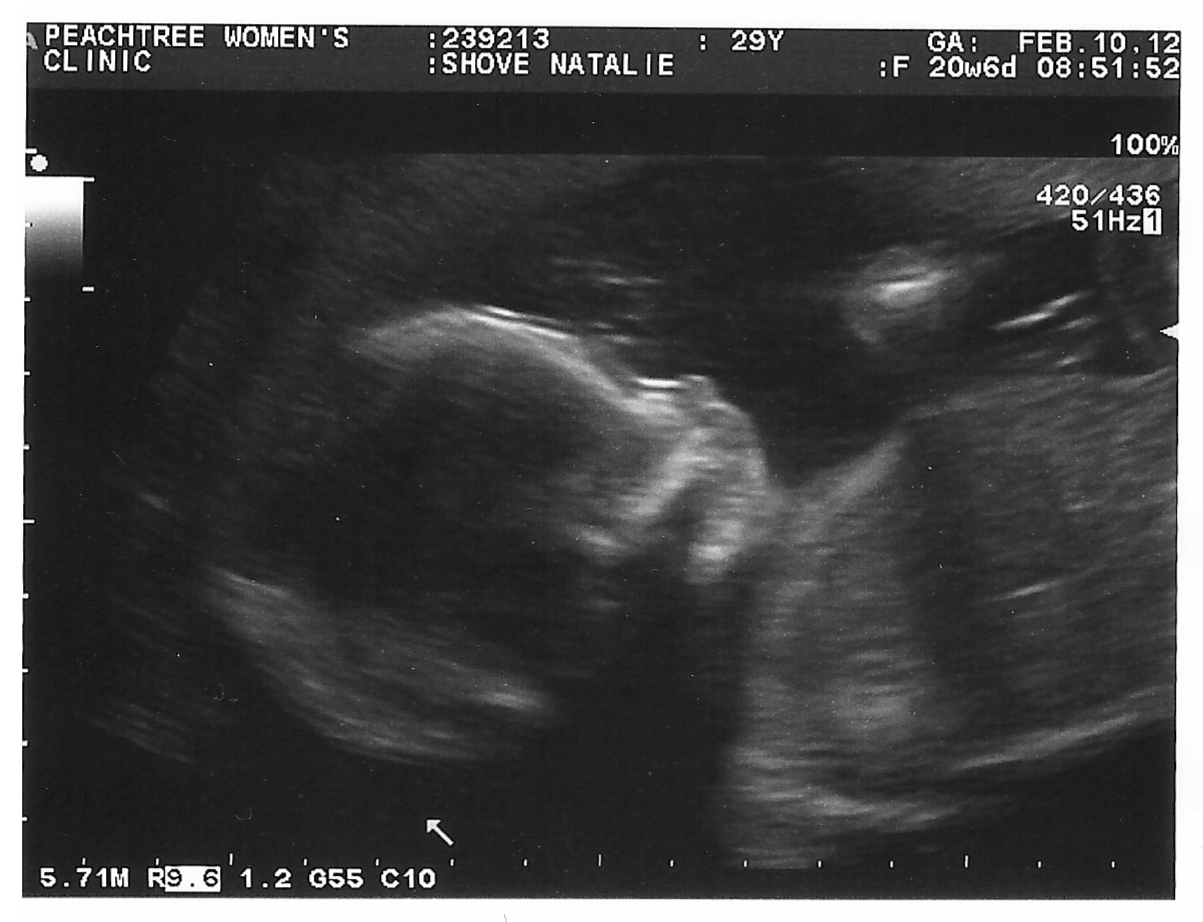

Last Friday we had our “20 week” appointment (which was more like 20-weeks-6-days, which, until I got pregnant, I never really thought mattered; in fact I always wondered when asked how far along a mom was why they didn’t just say “5 months,” but apparently it’s a big deal). Everything went really well; I had expected something to go wrong because everyone had warned me that something almost always comes up at this appointment, meriting another check up. But we had a great time, a great ultrasound tech, and a quick catch-up with the doctor about our previous worries, and we were done!

| 20 weeks, 6 days–right on target! |

Sidenote: Ultrasounds are amazing to me. Until I had my own, I (truthfully) never got that “Awww!” feeling about anyone else’s, but there’s something about actually seeing the baby move in real time (not just a picture print-out) that elicits a total adrenaline rush. I have a really hard time sitting still and not laughing during them! From this profile pic, I think this kid’s got the Aquilio nose…